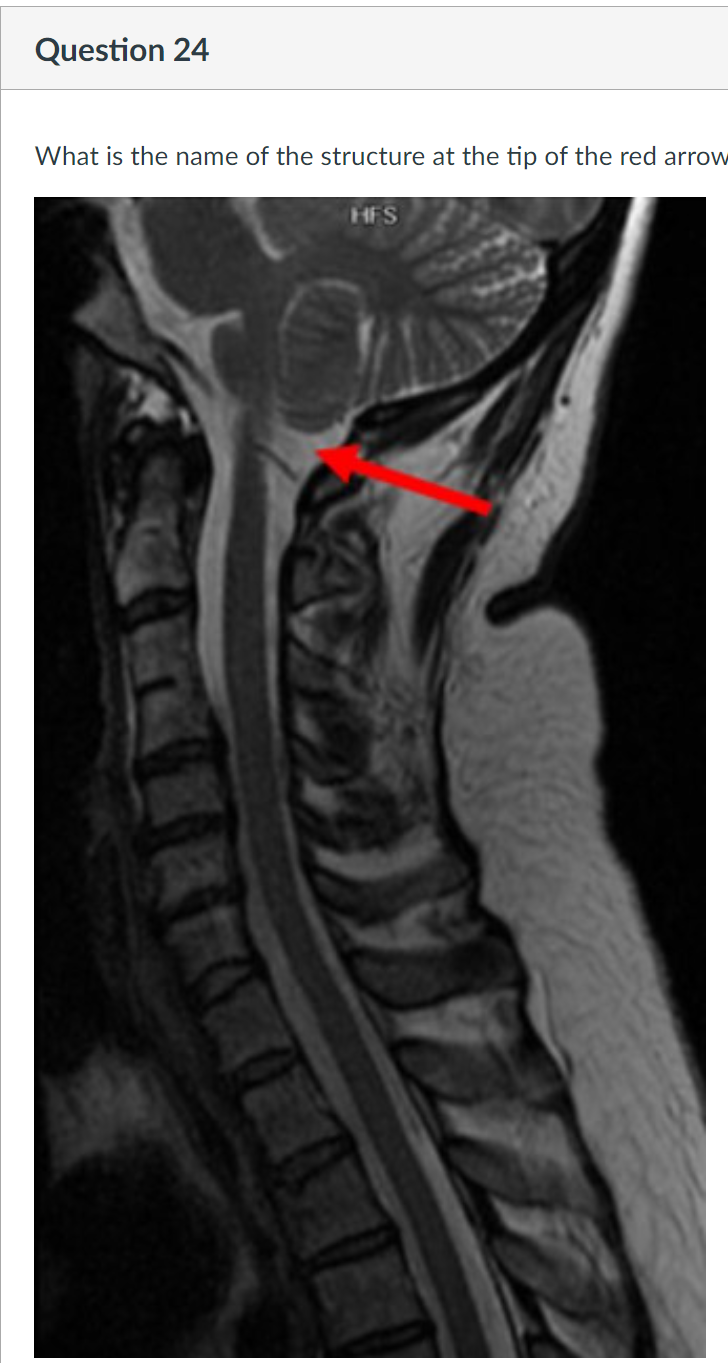

24

3rd cervical vertebra 3rd vertebral body